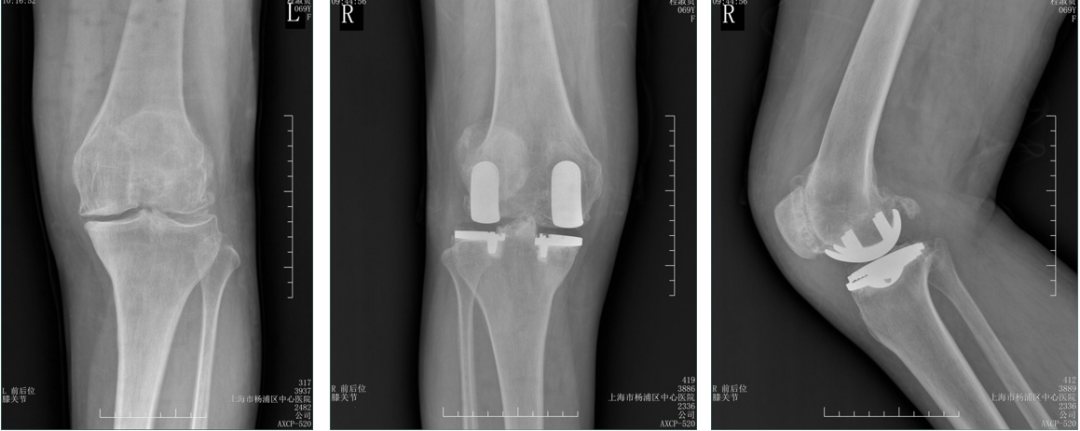

正位片标准胫骨和股骨假体位置

AP位假体位置:胫骨假体无明显内外翻,与胫骨轴线垂直,内侧缘与胫骨平台内侧缘齐平; 股骨假体长轴与胫骨假体垂直,中线一致。

侧位片标准胫骨和股骨假体位置

侧位片假体位置:股骨假体长栓与短栓平行,后倾35°;假体后缘与股骨后髁齐平,胫骨假体后倾7°,与胫骨平台前后缘齐平。